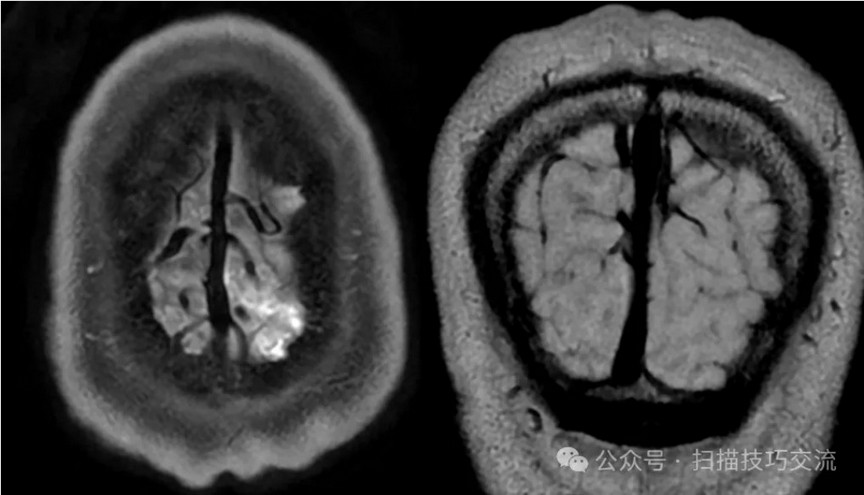

临床申请:颅脑平扫,静脉成像,磁敏感成像,颅内静脉血管黑血成像。

PC-MRV未见异常。